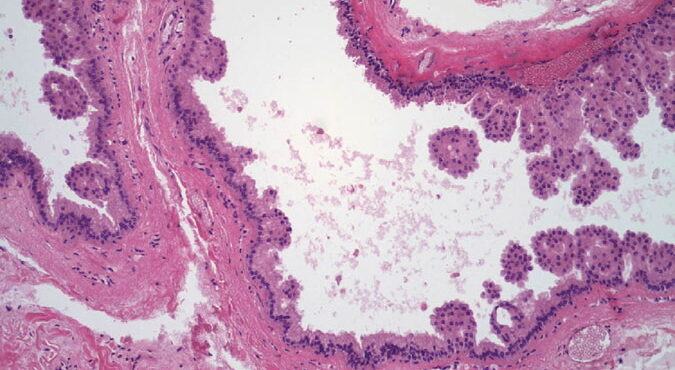

Herpes simplex = العقبول البسيط